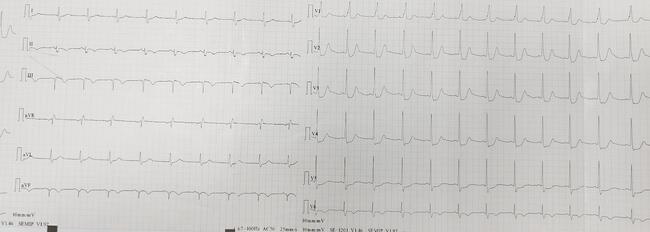

Occluded Left Circumflex Artery in a Patient With the de Winter Sign on Electrocardiography

Video Supplement to "Occluded Left Circumflex Artery in a Patient With the de Winter Sign on Electrocardiography" (Clinical Image).